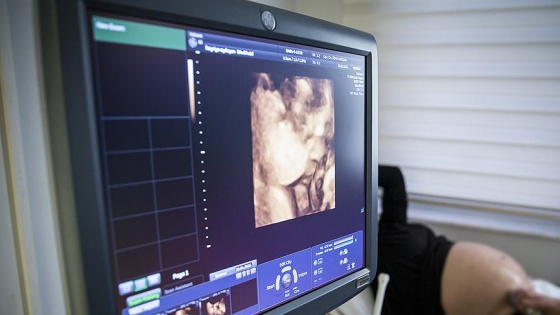

Türk bilim insanı Prof. Dr. Polat Dursun tarafından, plasenta yapışmasına bağlı yüksek kan kaybı nedeniyle doğumda anne ölümlerini azaltmaya yönelik geliştirilen yöntem, tıp literatürüne girdi.

Kadın hastalıkları ve doğum uzmanı Prof. Dr. Dursun'un "Bulldog Klemp" isimli ameliyat tekniği, dünyanın saygın bilimsel dergilerinden "Uluslararası Jinekoloji ve Obstetrik Dergisi"nin (International Journal of Gynecology ve Obstetrics) özel sayısında yayımlandı. Derginin YouTube kanalına da eğitim videosu olarak konulan yöntem uzmanların bilgisine sunuldu.

Prof. Dr. Dursun, AA muhabirine yaptığı açıklamada, plasentanın "gebeliğin ilk haftalarından itibaren anne ve bebek arasındaki besin alışverişini sağlayan organ" olarak tanımlandığını söyledi.

Plasenta yapışmasının erken tanı konulmasıyla düzenli takip ve tecrübeli bir ekiple başarılı bir şekilde yönetilebildiğini vurgulayan Dursun, tanı konulmadan sezaryene alınan anne adaylarında, bu durumun ameliyat sırasında aşırı kan kaybına ve çok fazla kan transfüzyonu (nakli) yapılmasına neden olduğunu anlattı.

Dursun, aşırı kan kaybının anne ölümlerine yol açtığının altını çizerek, plasenta yapışması tanısı konulan hastaların doğumlarının, mutlaka donanımlı, kan merkezi olan hastanelerde ve tecrübeli ekip tarafından yaptırılması gerektiğini söyledi.

Geliştirdiği plasenta yapışıklığı tespit edilen kadınlarda uygulanan yöntemle, doğumda bu soruna bağlı aşırı kanama nedeniyle ölüm riskinin büyük oranda azaltılabildiğine işaret eden Dursun, şöyle devam etti:

"(Bulldog Klemp) diye isimlendirilen yöntemle, anne adayının leğen kemiği içindeki organları besleyen damarlar, ameliyat süresince geçici olarak kapatılıyor. Bulldog Klemp denen metalik klemplerle leğen kemiği içindeki ana damara klip takılıyor ve damarın kan akımı geçici olarak kesiliyor ve ardından ameliyat gerçekleştiriliyor. Damarların kapatılmasıyla kanamanın çok az olması sağlanıyor.

Bu şekilde, doğum esnasında ve plasentanın ayrışması sırasında kanama kontrol altına alınabiliyor çünkü kan akımı çok az olduğu için hastaların kanaması da çok az oluyor. Bazen 20-30 ünite kan verilirken, bu yöntemle yaptığımız hastalarda 1-2 ünite kan veriliyor, bazen de buna bile gerek duyulmuyor. Ameliyat bitince klemp damardan çıkartılıyor. Ameliyat 1,5-2 saat sürüyor. Biz yöntemi sadece plasenta yapışıklığı olan kadınlarda kullandık ama normal doğum sonrası kanamalarda da kullanılabilir."